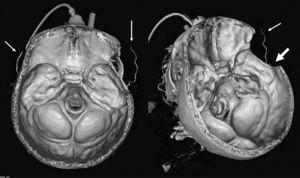

La angiografía computarizada constató en todos los casos la detención del contraste al nivel del agujero magno sin visualizarse contraste en arterias vertebrales intracraneales. Al estudiar la circulación anterior se visualiza un afilamiento progresivo de las arterias carótidas internas en el cuello, comprobándose que el contraste se detiene en la porción petrosa carotídea, y demostrándose la ausencia de relleno de las arterias carótidas internas intracraneales. Se observa relleno de contraste en las diferentes ramas de las arterias carótidas externas (figs. 1-4).

Figura 3. Reconstrucción 3D con supresión del hueso, donde se evidencia la parada del flujo en las arterias carótidas internas (flecha gruesa) y arterias vertebrales (flecha fina) a nivel extracraneal. Se visualizan las arterias carótidas externas y sus ramas (doble flecha).